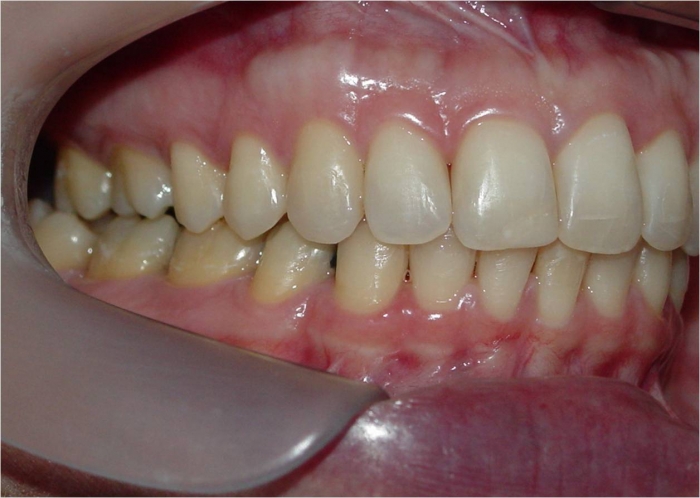

Mordida inicial